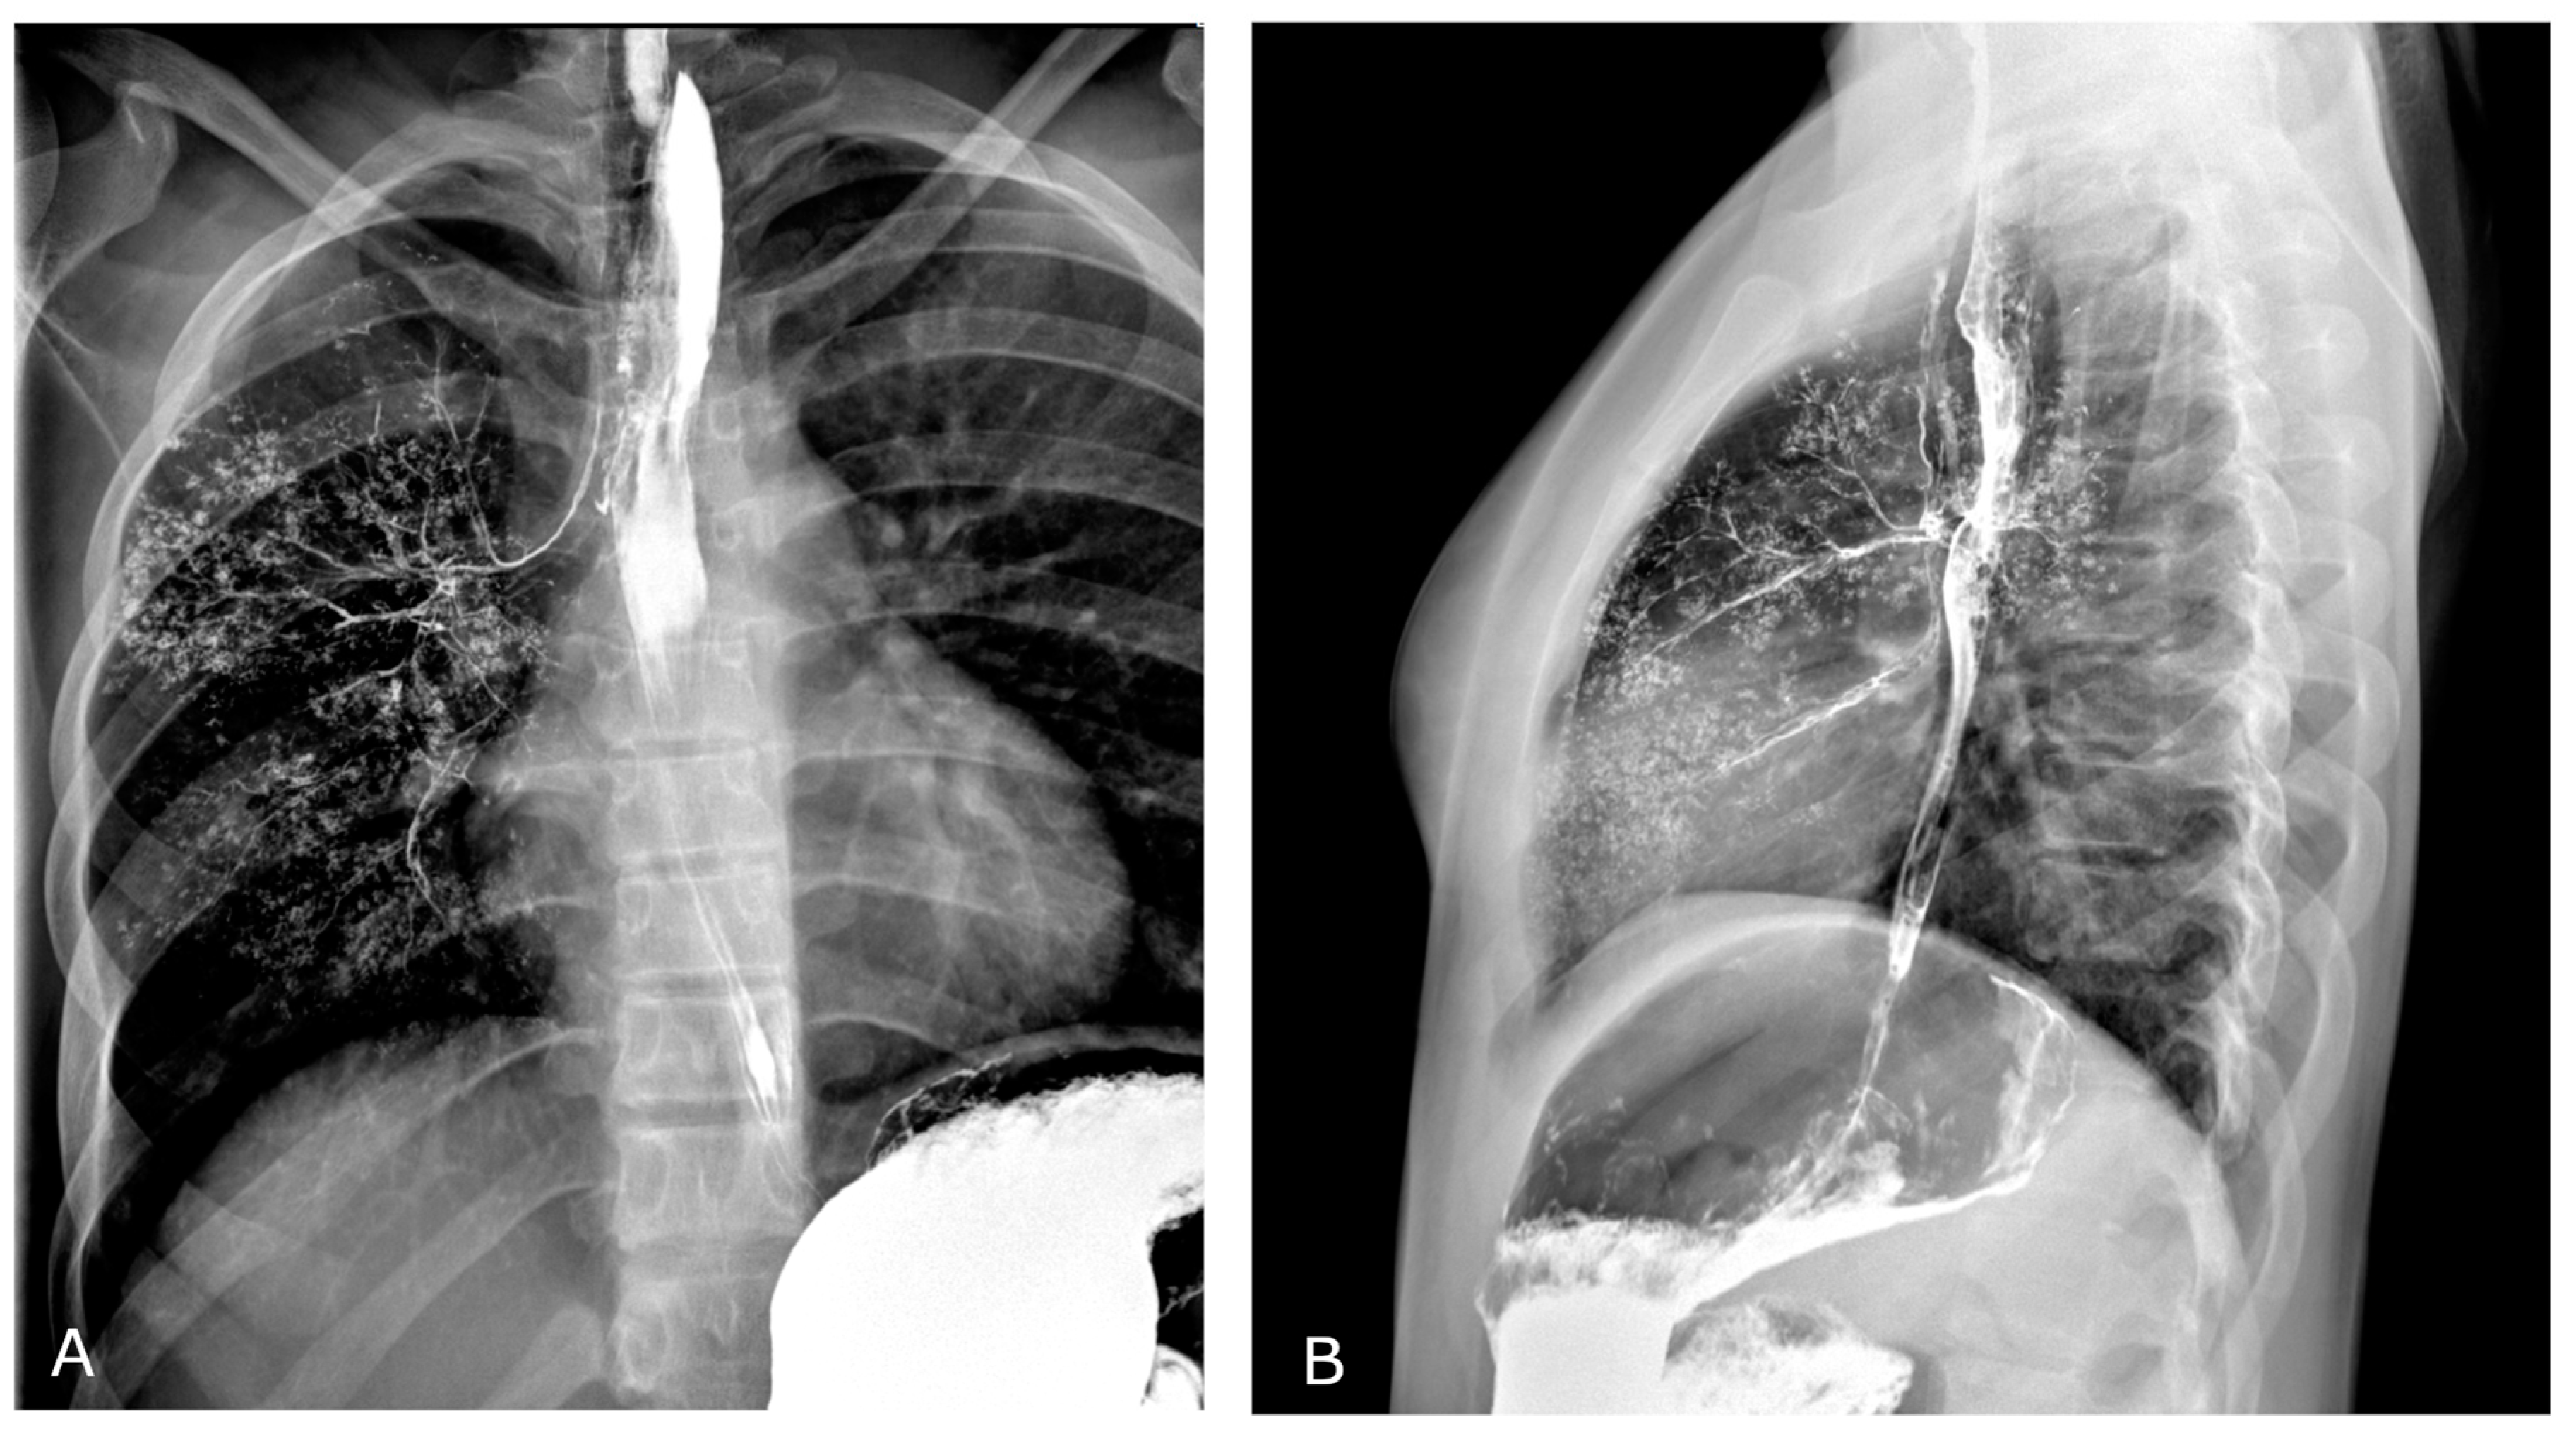

Figure 4.

Barium-swallowing study performed two years before (study recovered from patient’s medical record and performed in a different institution). Frontal (A) and lateral (B) views show opacification of right bronchial tree due to transit of barium-containing contrast agent through a small tracheoesophageal fistula.